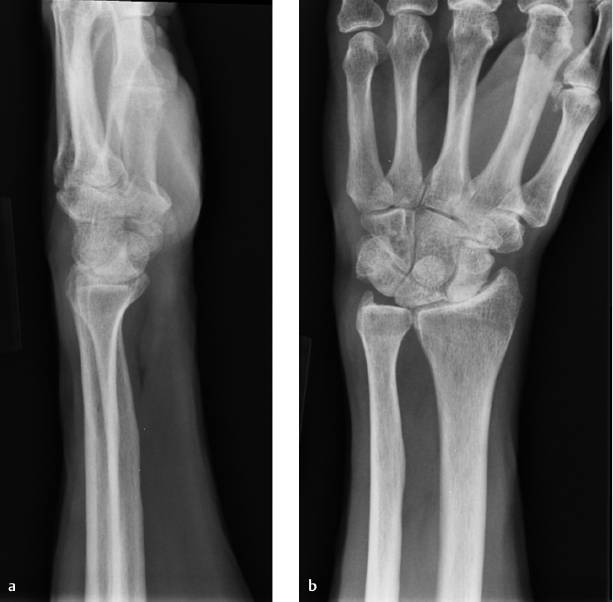

Advanced scapholunate advanced collapse (SLAC) (stage II) (► Fig. 58.1) or scaphoid nonunion advanced collapse (SNAC) (stage II or stage III if lunate and capitate preserved).